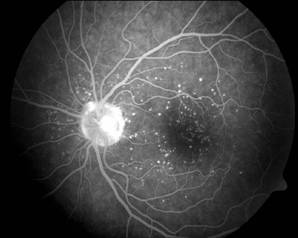

Miopia maligna

Este mult mai rara. este o anomalie congenitala, adeseori transmisibila genetic dominant. Tulburarea de refractie este prezenta de la nastere cu valori dioptrice mari, peste -10dpt.. Progreseaza tot timpul vietii, intermitent, pana la valori dioptrice mari: -20 pana la -30 si mai mult.

Simptomatologia functionala:

- acuitatea vizuala scazuta chiar si cu lentile corectoare deoarece corectia optica aeriana nu poate fi niciodata totala: imaginea retiniana ce s-ar forma prin lentilele corespunzatoare unor valori dioptrice mari de miopie ar fi sub dimensiunea minimum vizibil;

- campul vizual este redus concentric pentru alb si culori, se constata o largire a petei oarbei si scotoame uneori;

- simtul luminos este sub normal: hemeralopie la mari miopii, examenul simtului cromatic evidentiaza deficiente pentru albastru; .

Simptomatologia obiectiva:

modificarile patologice intereseaza toate structurile oculare. Pe masura ce leziunile degenerative progreseaza, apare o scadere a acuitatii vizuale, progresiva.

Complicatii: cataracta complicata, 1 uxatia cristalinului, dezlipirea de

retina. Miopia degenerativa se poate asocia cu malformatii genetice ale segmentului anterior al ochiului (colobom irian, glaucom congenital tardiv) sau al segmentului posterior al ochiului (degeneresceniie tapeto-retiniene, hemeralopia congenitala). Asociatia miopiei cu glaucomul cu unghi deschis

ridica probleme in privinta dificultatilor de depistare: scaderea rigiditatii sclerale caracteristica miopiei risca sa mascheze o hipertensiune intraoculara moderata. De aici decurge necesitatea examenului tensiunii intraoculare prin aplanatie.

Tratament optic: se recomanda corectie subtotala avand in vedere faptul ca lentila biconcava, ce-ar permite corectia totala, reduce dimensiunea imaginii retiniene sub minimum vizibil. Pentru ameliorarea acuitatii vizuale se recomanda lentile de contact, care permit o corectie mai apropiata de valoarea totala a miopiei. Pentru lectura se poate indica o corectie diferentiala si la varste mai tinere.